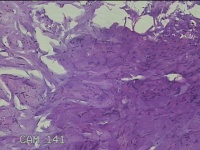

肛周外痔

1.出血性内痔 2.混合痔 3.肛乳头肥大

一般病史

间断便血3年余。

标本名称

大体所见

灰白暗红色包块0.7x0.3x0.2cm一个,表面糜烂。

像痔。

有可能是外痔。猜的。